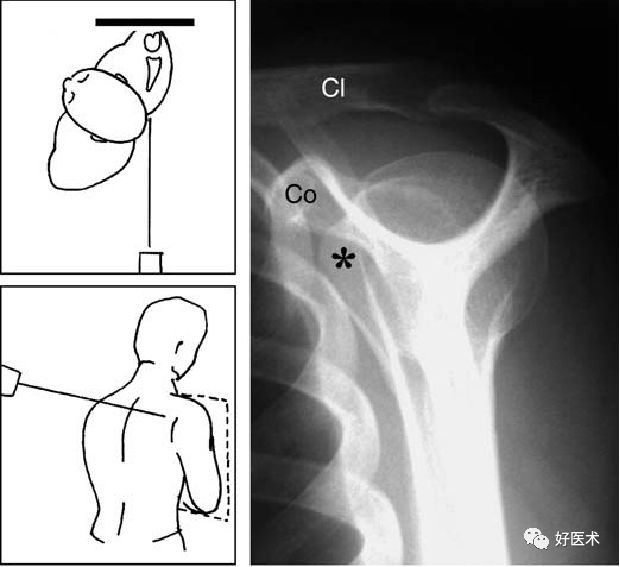

Bernageau位

肩关节前颅位

肩关节腋窝位

对关节盂的上部及后部、肩胛颈的正切显像

-

同时对盂肱关节位置关系、肩锁关节较精确的评估